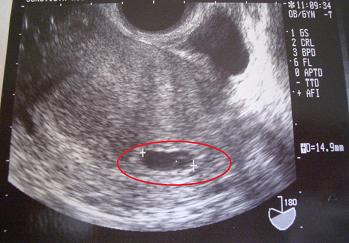

妊娠検査薬は、上から31日目(4w0d)、33日目(4w2d)、35日目(4w4d)。

妊娠確認時のエコー写真です。